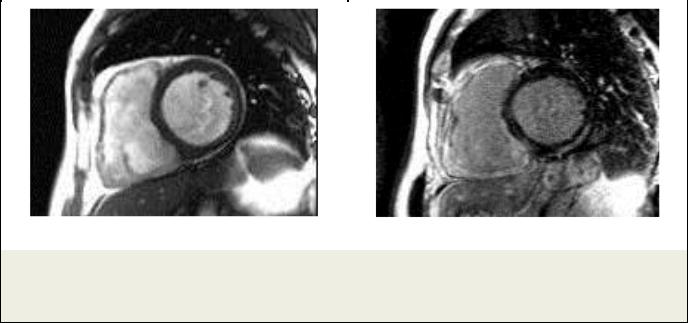

Рис. 9. МРТ сердца.

Пациент Т., амилоидоз сердца. Короткая ось ЛЖ. а – Кино-МРТ, симметричная гипертрофия миокарда ЛЖ. б – Отсроченное контрастирование, циркулярное субэндокардиальное накопление КС.

Рис. 10. МРТ сердца.

Пациент О., нарушение обмена гликогена – болезнь Данона. а – Короткая ось ЛЖ. Т1-ВИ; обращает внимание симметричная гипертрофия миокарда ЛЖ. б – Отсроченное контрастирование. Видны обширные зоны накопления контрастного препарата в боковой и нижней стенках.